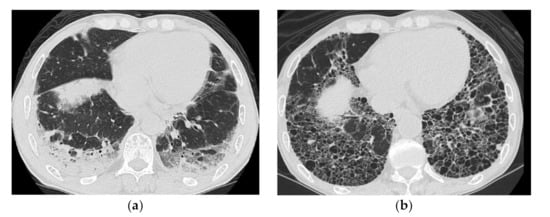

2.2. Acute Type

HRCT Findings of Patients with Anti-MDA5 Ab

| Reticular shadows and consolidation are common | GGO and consolidation |

| Good response to treatment but relapses | GGO and consolidation |